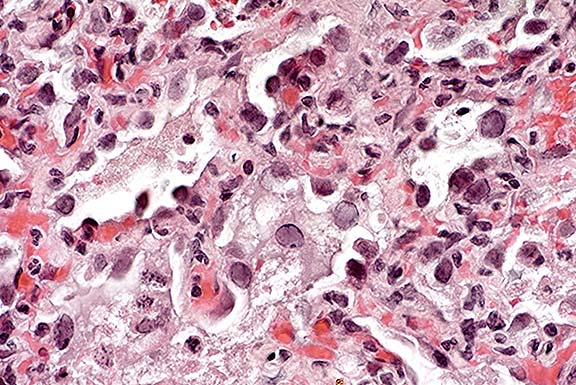

Case 14-1a. Lung. Mixed leukocytes and fibrin expand the interstitium with serofibrinous exudate and alveoli contain sloughing type II pneumocytes with diffuse basophilic nuclear inclusions. 40X

1. Lung: Pneumonia, interstitial, subacute, diffuse, moderate, with type II pneumocyte hyperplasia and intranuclear amphophilic to basophilic inclusion bodies, pig-tailed macaque (Macaca nemestrina), primate.

Lung lesions consist of patchy areas of interstitial pneumonia characterized by variable septal thickening due to congestion or histiocytic or fibroblast infiltration. Affected alveoli are lined by hyperplastic and hypertrophied type II pneumocytes, some of which contain intranuclear inclusion bodies.

2. Lung: Pneumonia, interstitial, fibrinous, subacute, diffuse, severe, with type II pneumocyte hyperplasia and intraepithelial, basophilic intranuclear inclusions.